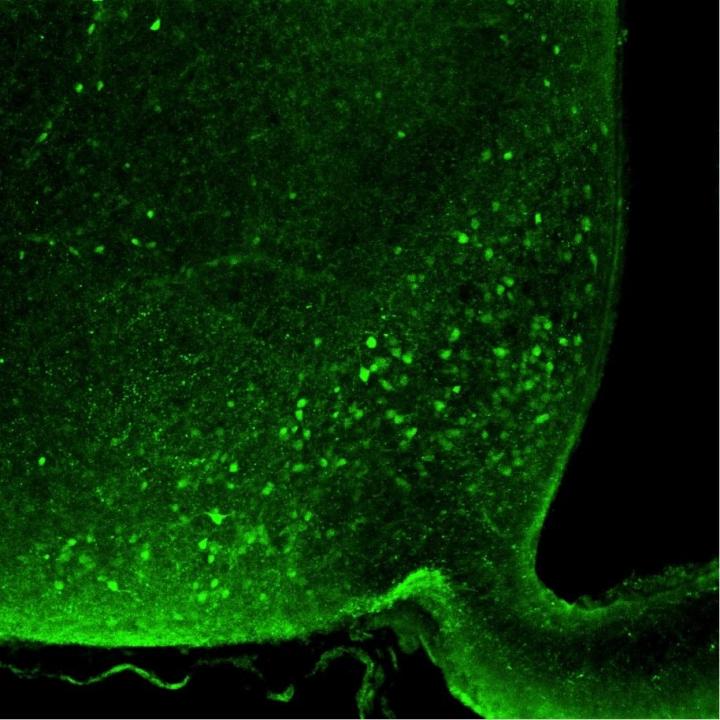

image: Nociceptin neurons in the arcuate nucleus of the hypothalamus. view more

Credit: MPI f. Metabolism Research

Since the 1980s, we are seeing a worldwide increase in obesity and associated diseases such as diabetes mellitus and cardiovascular disease. Researchers from the Max Planck Institute for Metabolism Research from the laboratory of Jens Brüning have used mice in animal studies to investigate which nerve cells control the overeating of high-calorie, energy dense food. For this purpose, the animals were fed a high-fat diet and examined afterwards." Just three days of a high-fat diet feeding were sufficient to detect increased activity of nociceptin neurons in a specific region of the brain, the arcuate nucleus of the hypothalamus," says Alexander Jais, first author of the current study.